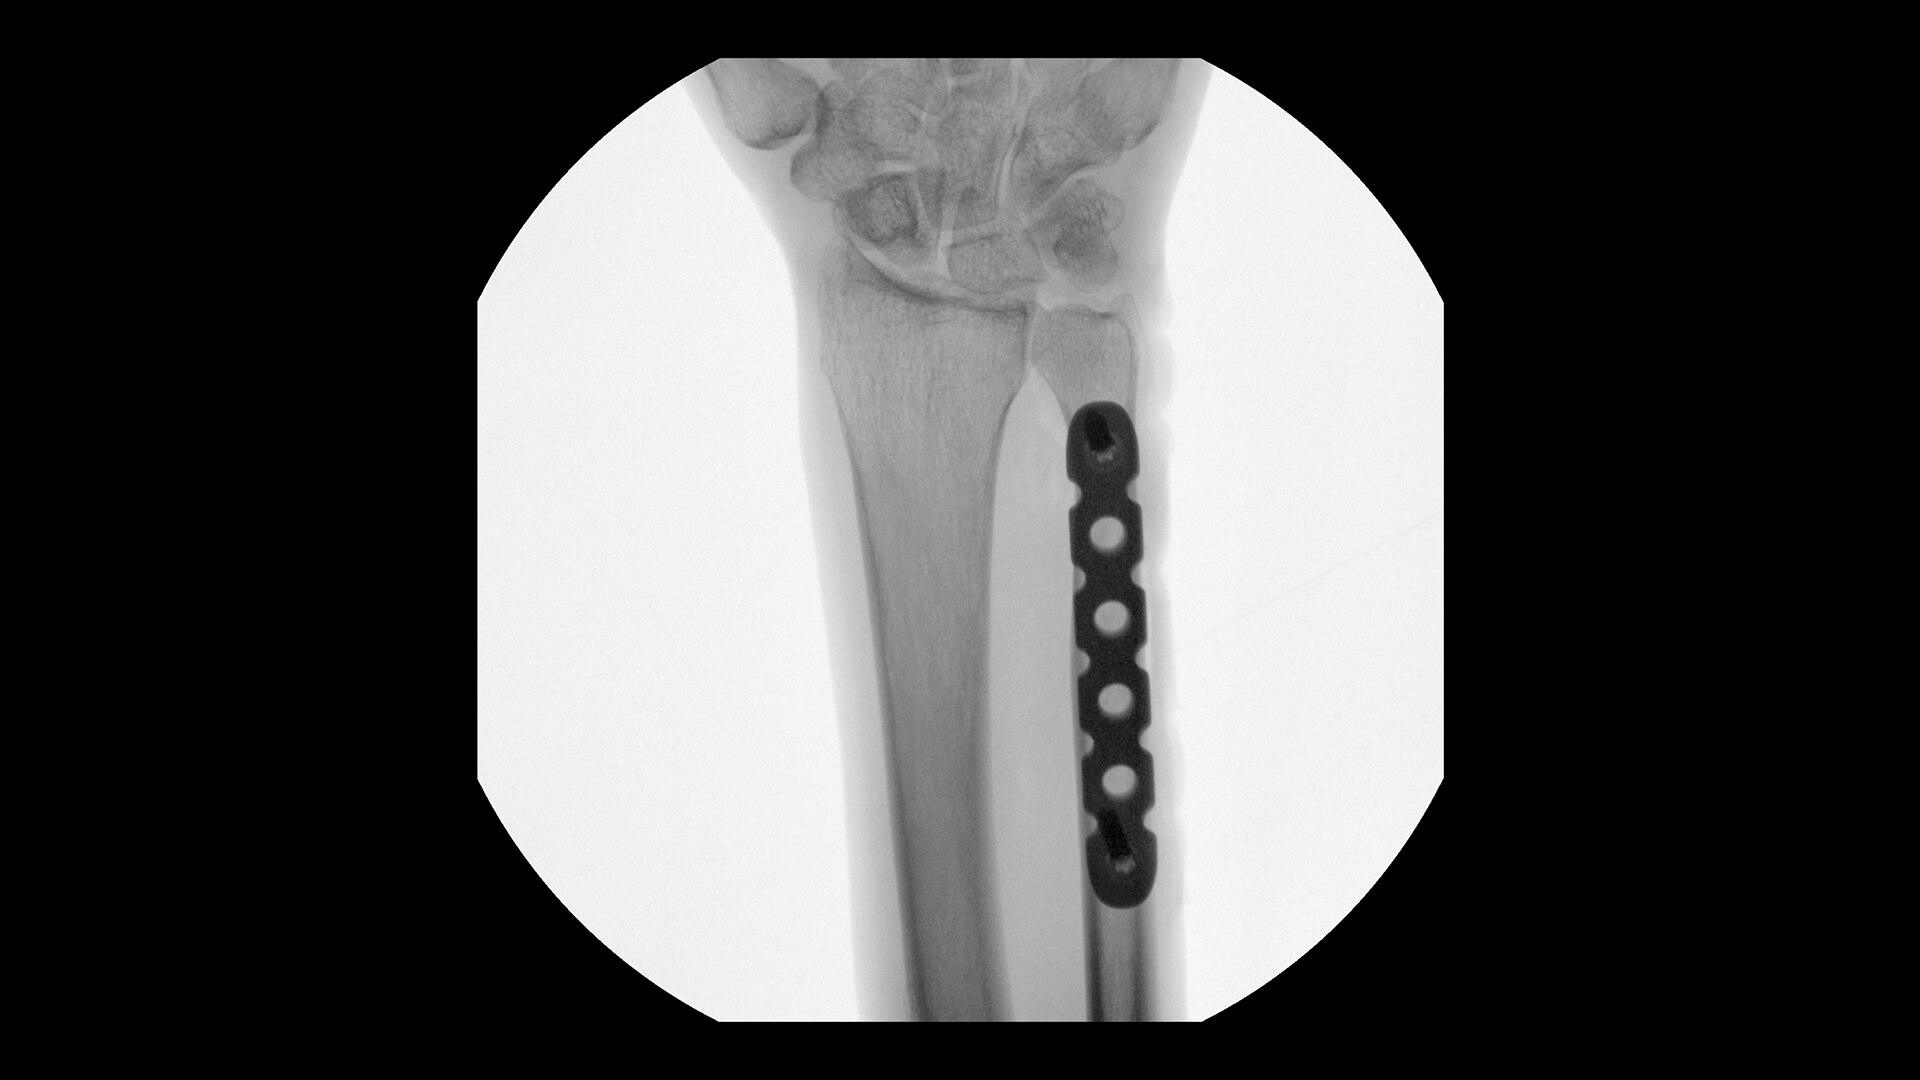

AUTO LINHAS-B

Destaque e conte linhas B em tempo real

Com a ferramenta de Auto Linhas-B você pode calcular o score pulmonar geral em uma etapa. Utilize em conjunto com o Lung Sweep para destacar linhas B e exibir o quadro com mais linhas B por espaço intercostal.